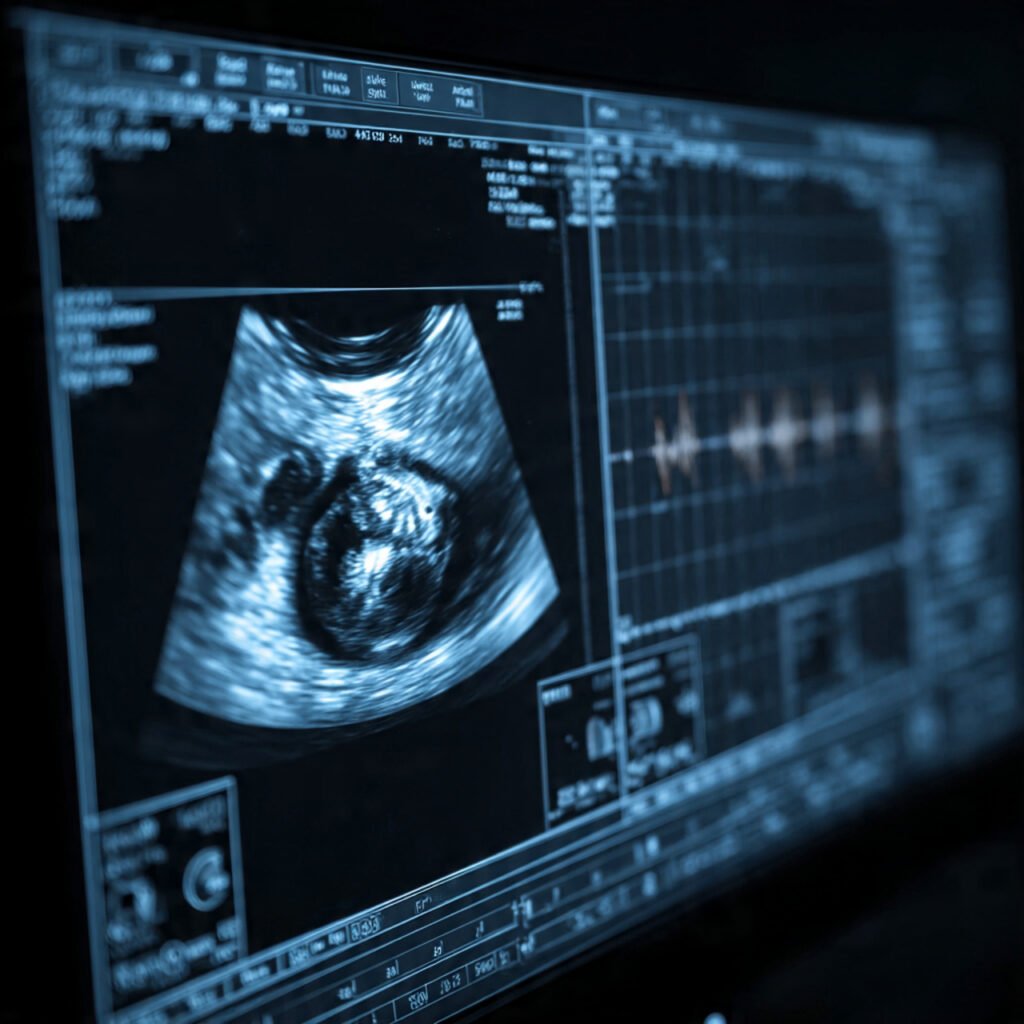

Pregnancy scans are an essential part of prenatal care. Many parents look forward to these scans because they provide the first glimpse of their growing baby. During these scans, doctors can evaluate the baby’s organs, bones, and overall development.

A pregnancy scan, also known as an ultrasound scan, uses sound waves to create images of the baby developing inside the uterus. These scans are safe for both the mother and the baby and are routinely performed throughout pregnancy.

However, a pregnancy scan can check the structure of the baby’s ears. During the scan, doctors can observe whether the ears are present and whether they appear structurally normal.

Ultrasound scans mainly assess physical structures, not functional abilities.